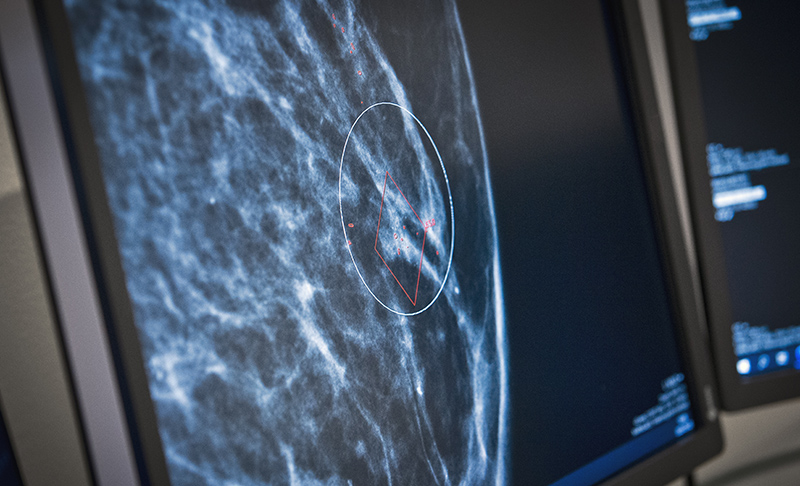

Först med AI i mammografiRegion Värmland är först i Sverige att använda artificiell intelligens vid mammografi.